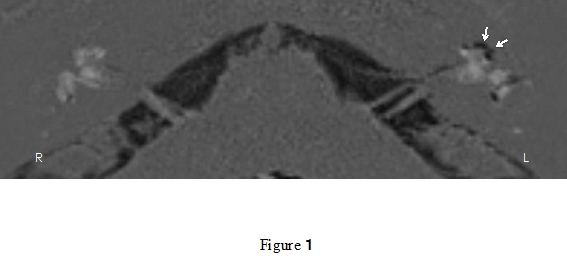

ii) Evaluation of inner ear on MRI

Visualization of endolymphatic hydrops has become available using 3T MRI with contrast agents (Figure 1). We have investigated the existence of endolymphatic hydrop in various ear disorders. We evaluate breakdown of blood-labyrinth barrier, which could be a factor for predicting prognosis of inner ear disturbances (Figure

2). The evaluation is also available to avoid complications following surgeries for cholesteatomas with labyrinthine fistulae.